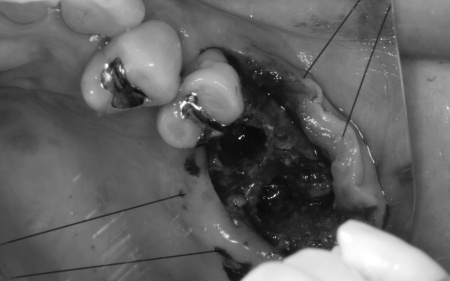

左上については、顎の骨が大きく失われているため、骨を再生させる処置「GBR(骨再生誘導法)」を実施してインプラントを支えるために必要な骨量を確保したうえで、インプラントを埋入する計画を立てました。

まずは左上奥歯2本を抜き、骨が足りない部分に骨補填剤を入れ骨の再生を促します。